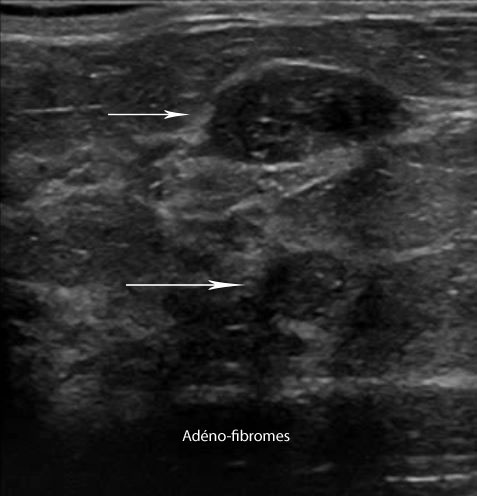

Elle précise donc une masse détectée en mammographie qui peut être liquide: kystique, solide: fibrome ou suspecte.

- ACR 2 : Il existe des anomalies bénignes ne nécessitant ni surveillance, ni examen complémentaire.